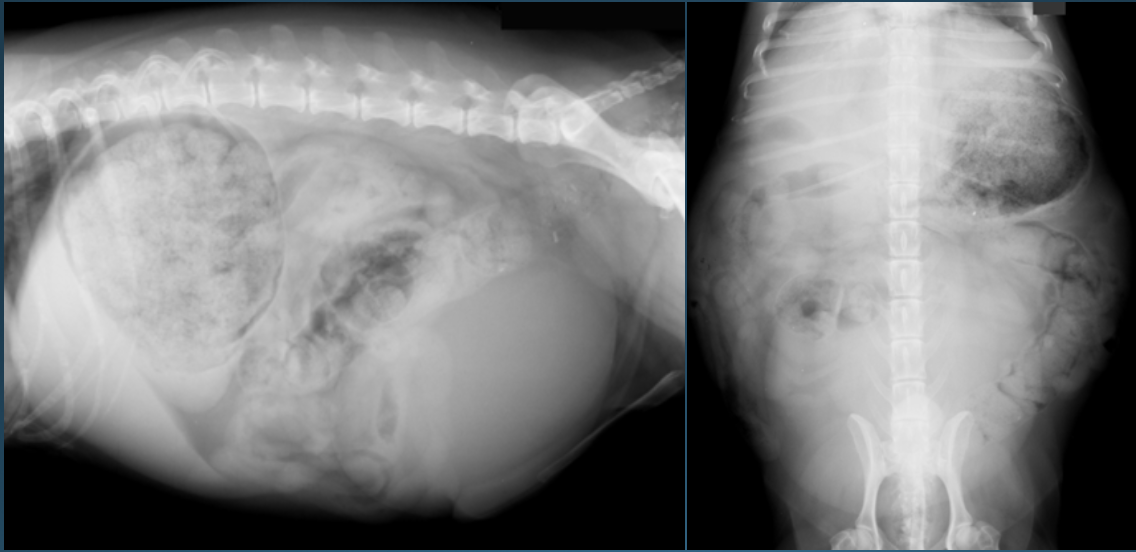

4

What is shown in this image?

normal abdomen in an obese cat